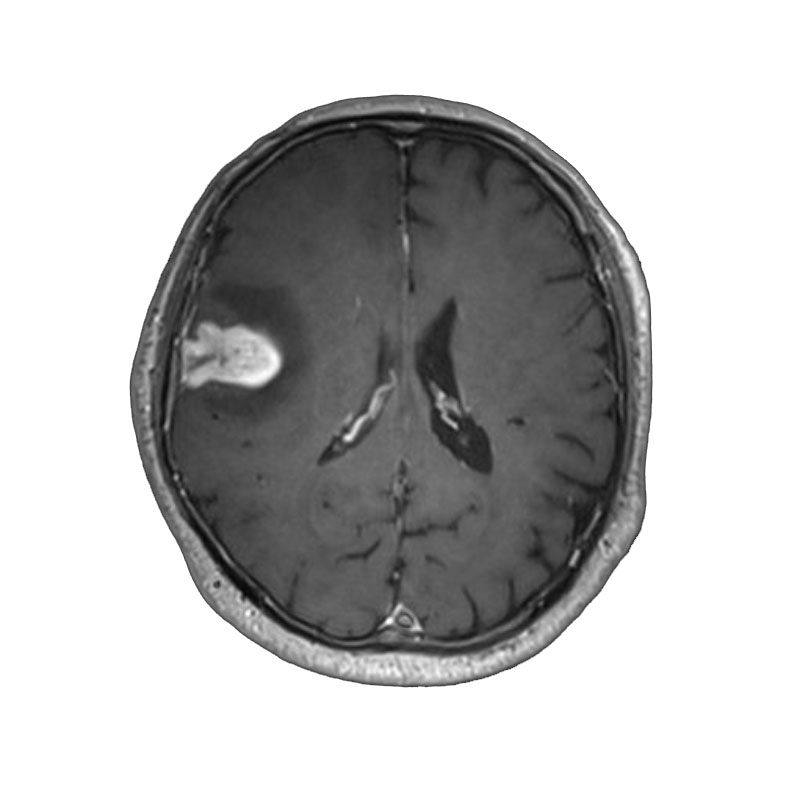

脳動脈瘤(Rt.MC)

クリッピング術

松田/濵田